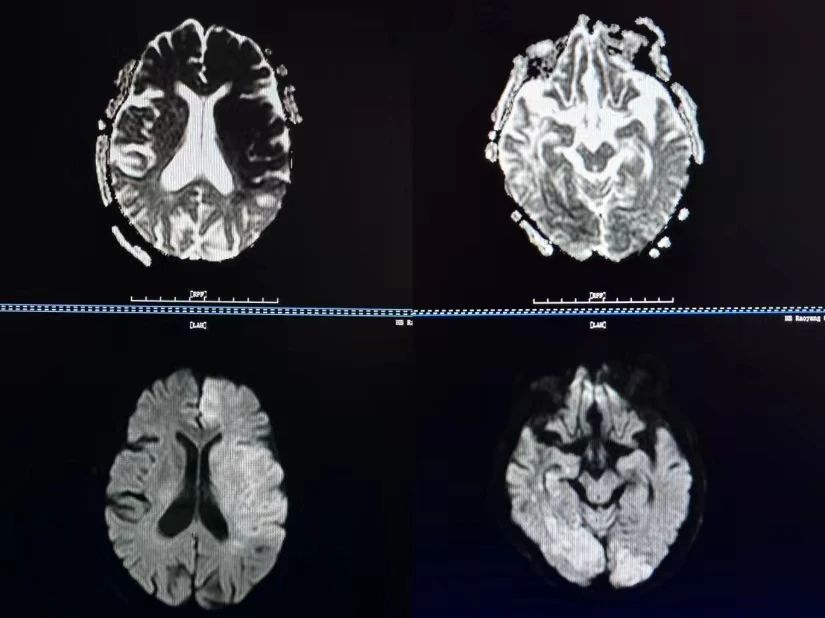

头颅磁共振弥散加权成像即头颅DWI,是功能磁共振的一种,可用于缺血性脑血管病的早期诊断,DWI扫描序列能发现磁共振其他序列无法检出的病灶,还能够对有些病变的鉴别诊断起到决定性的作用。DWI扫描序列在临床中的应用,主要体现在以下几个方面:

一是发现新发脑梗塞,检出新发脑梗塞,是DWI扫描序列应用最为成熟的一个方面,发病半小时就能够发现病灶,2小时肯定能发现病灶,而CT扫描需要24小时才能够发现病灶。

总之,DWI是磁共振临床应用中的一个非常重要的序列,当我们需要发现新发脑梗塞时,就进行DWI扫描;当我们检查脑外伤患者时,需要进行DWI扫描;当我们需要鉴别病变的良恶性时、对表皮样囊肿、脑脓肿等疾病定性诊断时,我们要进行DWI 扫描。